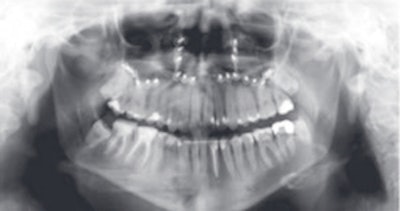

Imaging in these patients is usually performed with 2D panoramic radiography, CT, or CBCT. However, MRI may represent a complementary imaging technique to visualize particular pathological processes, especially inflammatory disease of the periodontal space, or teeth vascularization after trauma, he said. His presentation focused on the potential of high-resolution MRI in this new field and compared it with CT and CBCT.

An example of cone-beam CT. In this instance, the lower left third molar (d. 38) was imaged after panoramic radiograph with CBCT. The arrows mark the mandibular canal. Images courtesy of Dr. Anni Suomalainen.

The CBCT technique is well-known among dentists and oral radiologists, but it's not so well-known among general radiologists. It's very important that general radiologists are familiar with this technique and that they know the indications for its use, according to Dr. Anni Suomalainen, from the radiology department at Helsinki University Central Hospital in Finland.